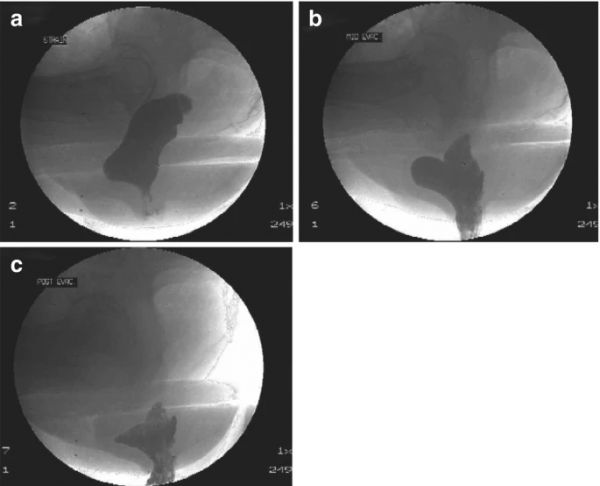

排便過(guò)程 圖(圖8.5 )是對(duì)不透射線(xiàn)的粥狀混合物進(jìn)行排便行為的 X 射線(xiàn)測(cè)試。它確定了直腸前突的部位和大?。ㄒ约捌渌毕荩?。如果造影劑在排便后被困在直腸前突中,這也會(huì)導(dǎo)致排便后弄臟(因?yàn)榧S便會(huì)慢慢從口袋中滲出)。它還顯示直腸套疊,這可能導(dǎo)致大便失禁和排便受阻。

圖 8.5

22541674169823346

排便程序圖。( a ) 直腸前突膨出進(jìn)入陰道。( b ) 排便,直腸前突“滯留”。( c ) 排便后膠片,對(duì)比劑困在前直腸前突 全尺寸圖片